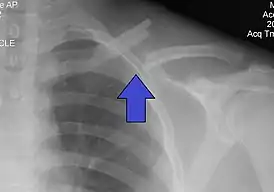

Перелом ключицы

Перелом ключицы — патологическое состояние, проявляющееся нарушением анатомической целостности ключицы. Чаще всего переломы происходят в средней трети на границе наружной и средней третей ключицы, на наиболее изогнутой и истонченной её части. Наиболее часто встречающиеся — косые и оскольчатые.

Выполняется рентген в прямой и боковой проекциях.